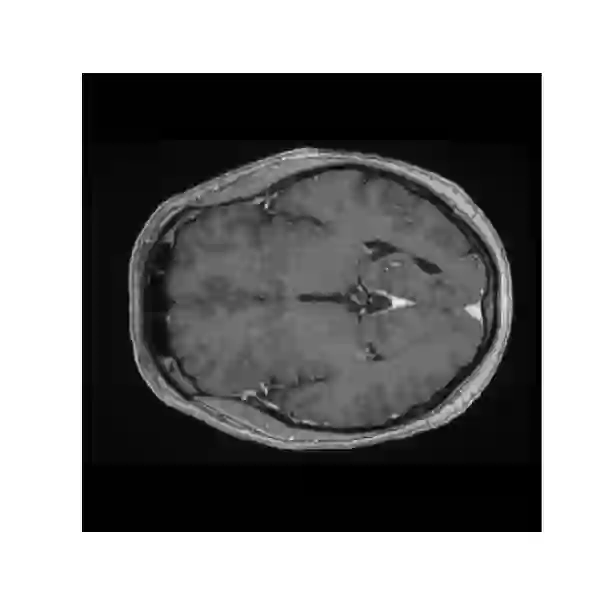

Objectives: Present a novel deep learning-based skull stripping algorithm for magnetic resonance imaging (MRI) that works directly in the information rich k-space. Materials and Methods: Using two datasets from different institutions with a total of 36,900 MRI slices, we trained a deep learning-based model to work directly with the complex raw k-space data. Skull stripping performed by HD-BET (Brain Extraction Tool) in the image domain were used as the ground truth. Results: Both datasets were very similar to the ground truth (DICE scores of 92\%-98\% and Hausdorff distances of under 5.5 mm). Results on slices above the eye-region reach DICE scores of up to 99\%, while the accuracy drops in regions around the eyes and below, with partially blurred output. The output of k-strip often smoothed edges at the demarcation to the skull. Binary masks are created with an appropriate threshold. Conclusion: With this proof-of-concept study, we were able to show the feasibility of working in the k-space frequency domain, preserving phase information, with consistent results. Future research should be dedicated to discovering additional ways the k-space can be used for innovative image analysis and further workflows.

翻译:提出磁共振成像(MRI)基于深层次学习的磁共振成像头骨剥离算法(MRI),该算法在信息丰富k-空间中直接发挥作用。材料和方法:利用来自不同机构的两套数据集,总共36 900 MRI片,我们训练了一个深层次学习模型,直接与复杂的原始K-空间数据合作。由HD-BET(Brain提取工具)在图像领域进行的Skull剥离过程被用作地面真相。结果:两个数据集都与地面真相非常相似(DICE分数92 ⁇ -98 ⁇ 和Hausdorff在5.5毫米以下的距离)。眼睛区域上的切片达到99 ⁇ 的DICE分数,而精度则在眼睛和下面区域下降,结果部分模糊。Kstrip的输出往往在头骨的标界边缘平滑。用一个适当的阈值创建了Binary面具。结论:通过这一检验研究,我们得以显示在K-空间频域内工作的可行性,保存阶段信息,并使用进一步探索K-空间图像的方法。